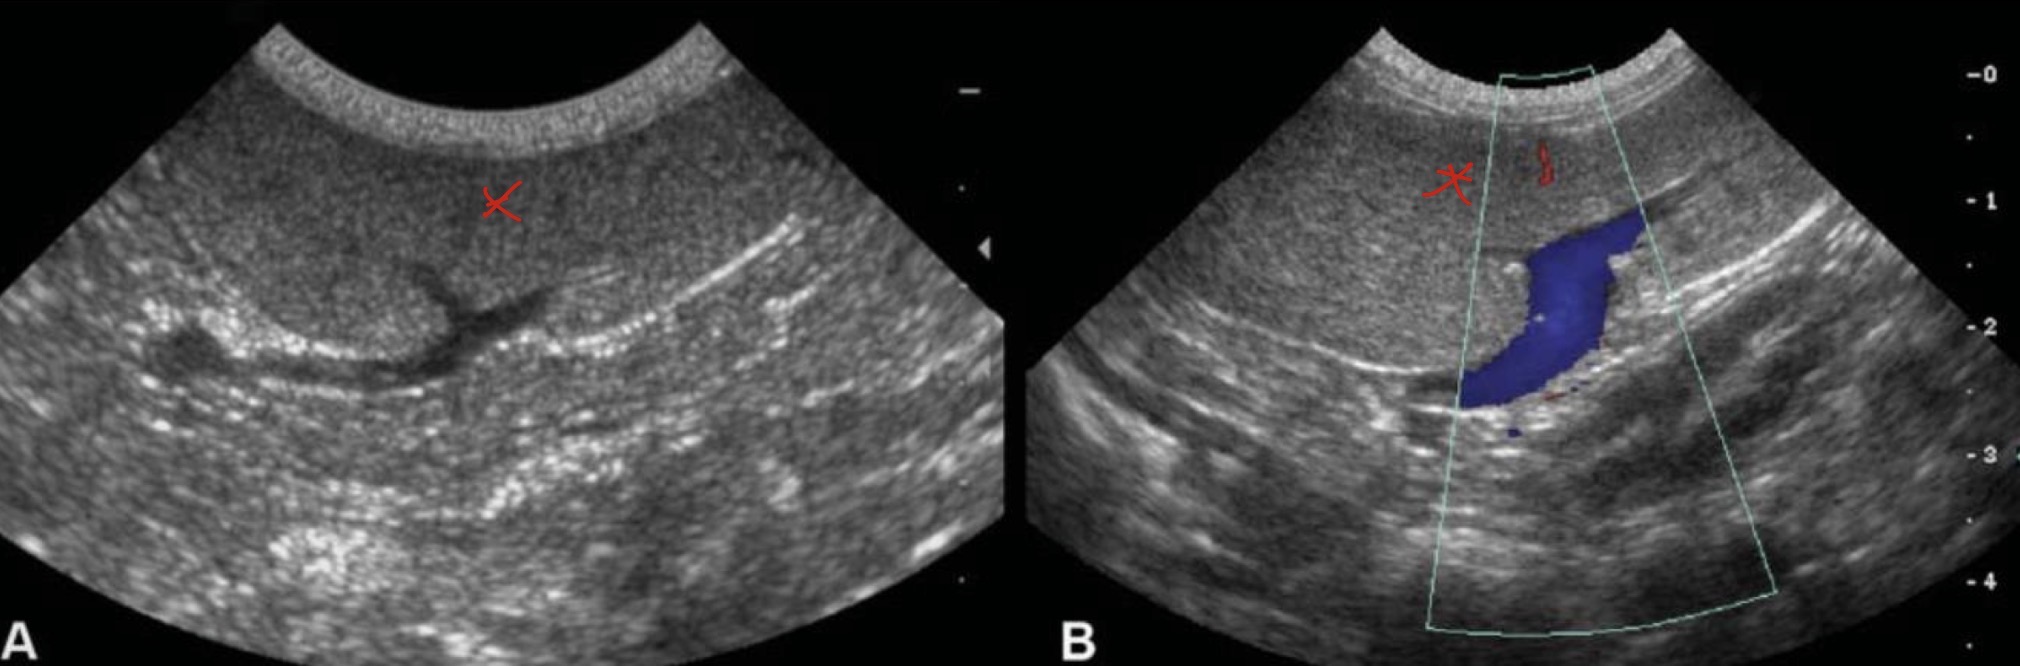

TCC

What is being depicted here?